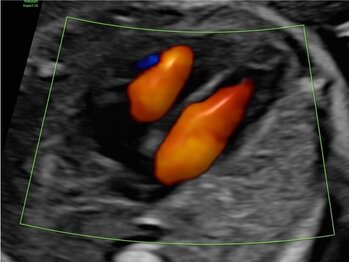

Ultraschalluntersuchung der mütterlichen und kindlichen Durchblutung (Farb-Dopplersonografie)

Die Durchblutung der Nabelschnur, der kindlichen Gefäße und des Mutterkuchens wird mittels einer speziellen Ultraschalltechnik durchgeführt. Mit der sogenannten (Farb-)Dopplersonografie können wir in der Pränataldiagnostik und Schwangerenambulanz die Versorgungslage überprüfen.

Auffällige Blutflussmuster können auf eine Mangelversorgung des Ungeborenen oder Auffälligkeiten im Kreislauf der Mutter hinweisen. Zu nennen wäre hier das erhöhte Risiko für einen schwangerschaftsbedingten Bluthochdruck. Mittels der Untersuchung können solche Probleme rechtzeitig erkannt und die Patientin entsprechend am UKS überwacht werden.

Nabelschnurarterie

Gehirndurchblutung (A. cerebri media)